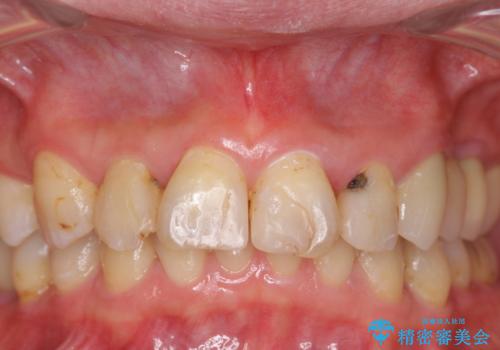

前歯の虫歯 つぎはぎの歯をセラミックに

- 矯正治療後に、前歯の樹脂の詰め物のやりかえを提案していましたが、治療は当時行いませんでした。

その後3年間来院がなく、その間に前歯の虫歯の進行があり、治療を行いました。

やはり、樹脂で虫食い状になってしまうと虫歯が進行しやすくなっているためクラウンがおすすめです。